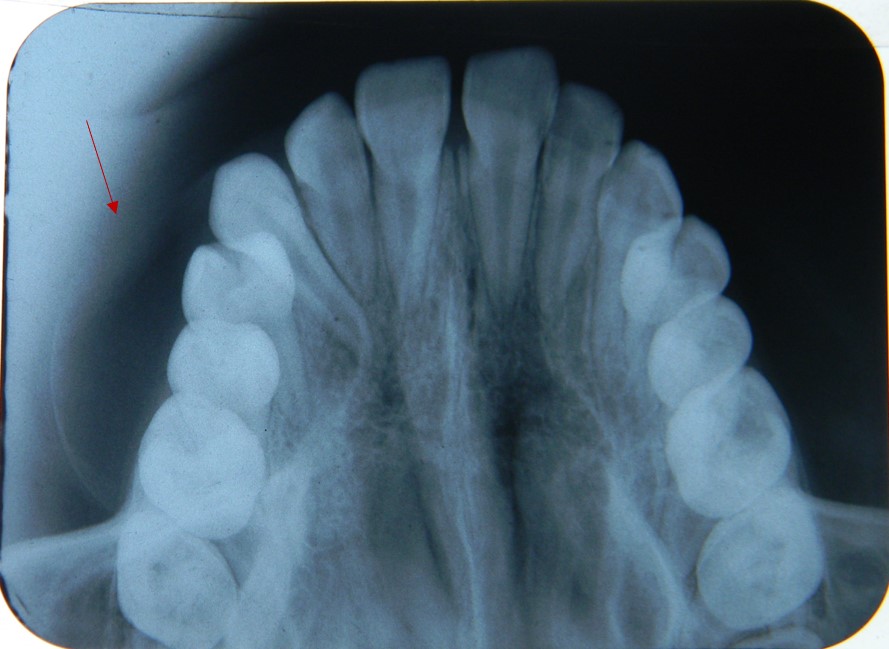

O cisto odontogênico calcificante (COC) foi primeiramente descrito em 1962, considerado como condição patológica benigna de ocorrência rara em maxila e mandíbula, caracterizado por revestimento cístico de células epiteliais odontogênicas contendo células fantasmas com propensão a regiões de calcificação. Neste artigo, descreveu-se a configuração clínica e histopatológica do COC por meio de relato de caso submetido a tratamento cirúrgico e acompanhamento pós-operatório. Uma paciente de 11 anos apresentou um aumento de volume em região maxilar a esquerda próxima ao sulco nasolabial sem sintomatologia dolorosa. Os exames radiográficos indicaram lesão radiolúcida, bem circunscrita e expansiva em maxila, que foi submetida a enucleação associada a ostectomia marginal das paredes corticais ósseas. O quadro histopatológico foi caracterizado por revestimento cístico com epitélio odontogênico ameloblástico, ninhos espalhados de células fantasmas e regiões eosinofílicas de material compatível com dentinóide. O relato de caso apresentou perfil clínico de COC, que pode ser confundido com outras lesões císticas ou tumorais, sendo essencial diagnóstico por meio de análise histopatológica. A abordagem cirúrgica proporcionou diagnóstico e tratamento. Após acompanhamento clínico e radiográfico, não houve recorrência do COC.